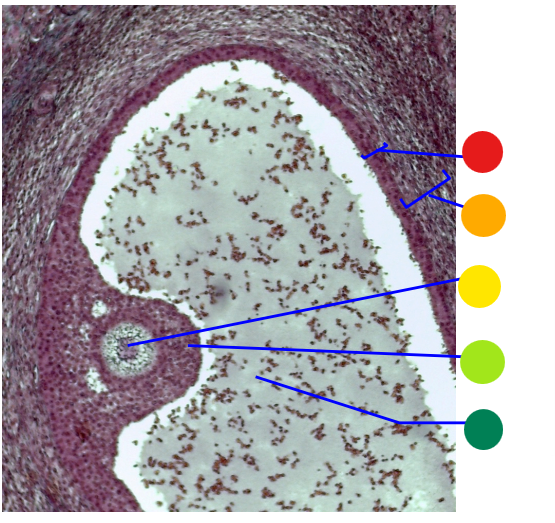

red

tunica albuginea

orange

primordial follicles

yellow

follicular cells

light green

primary oocyte

dark green

granulosa cells

light blue

primary follicles

what is this?

ovary